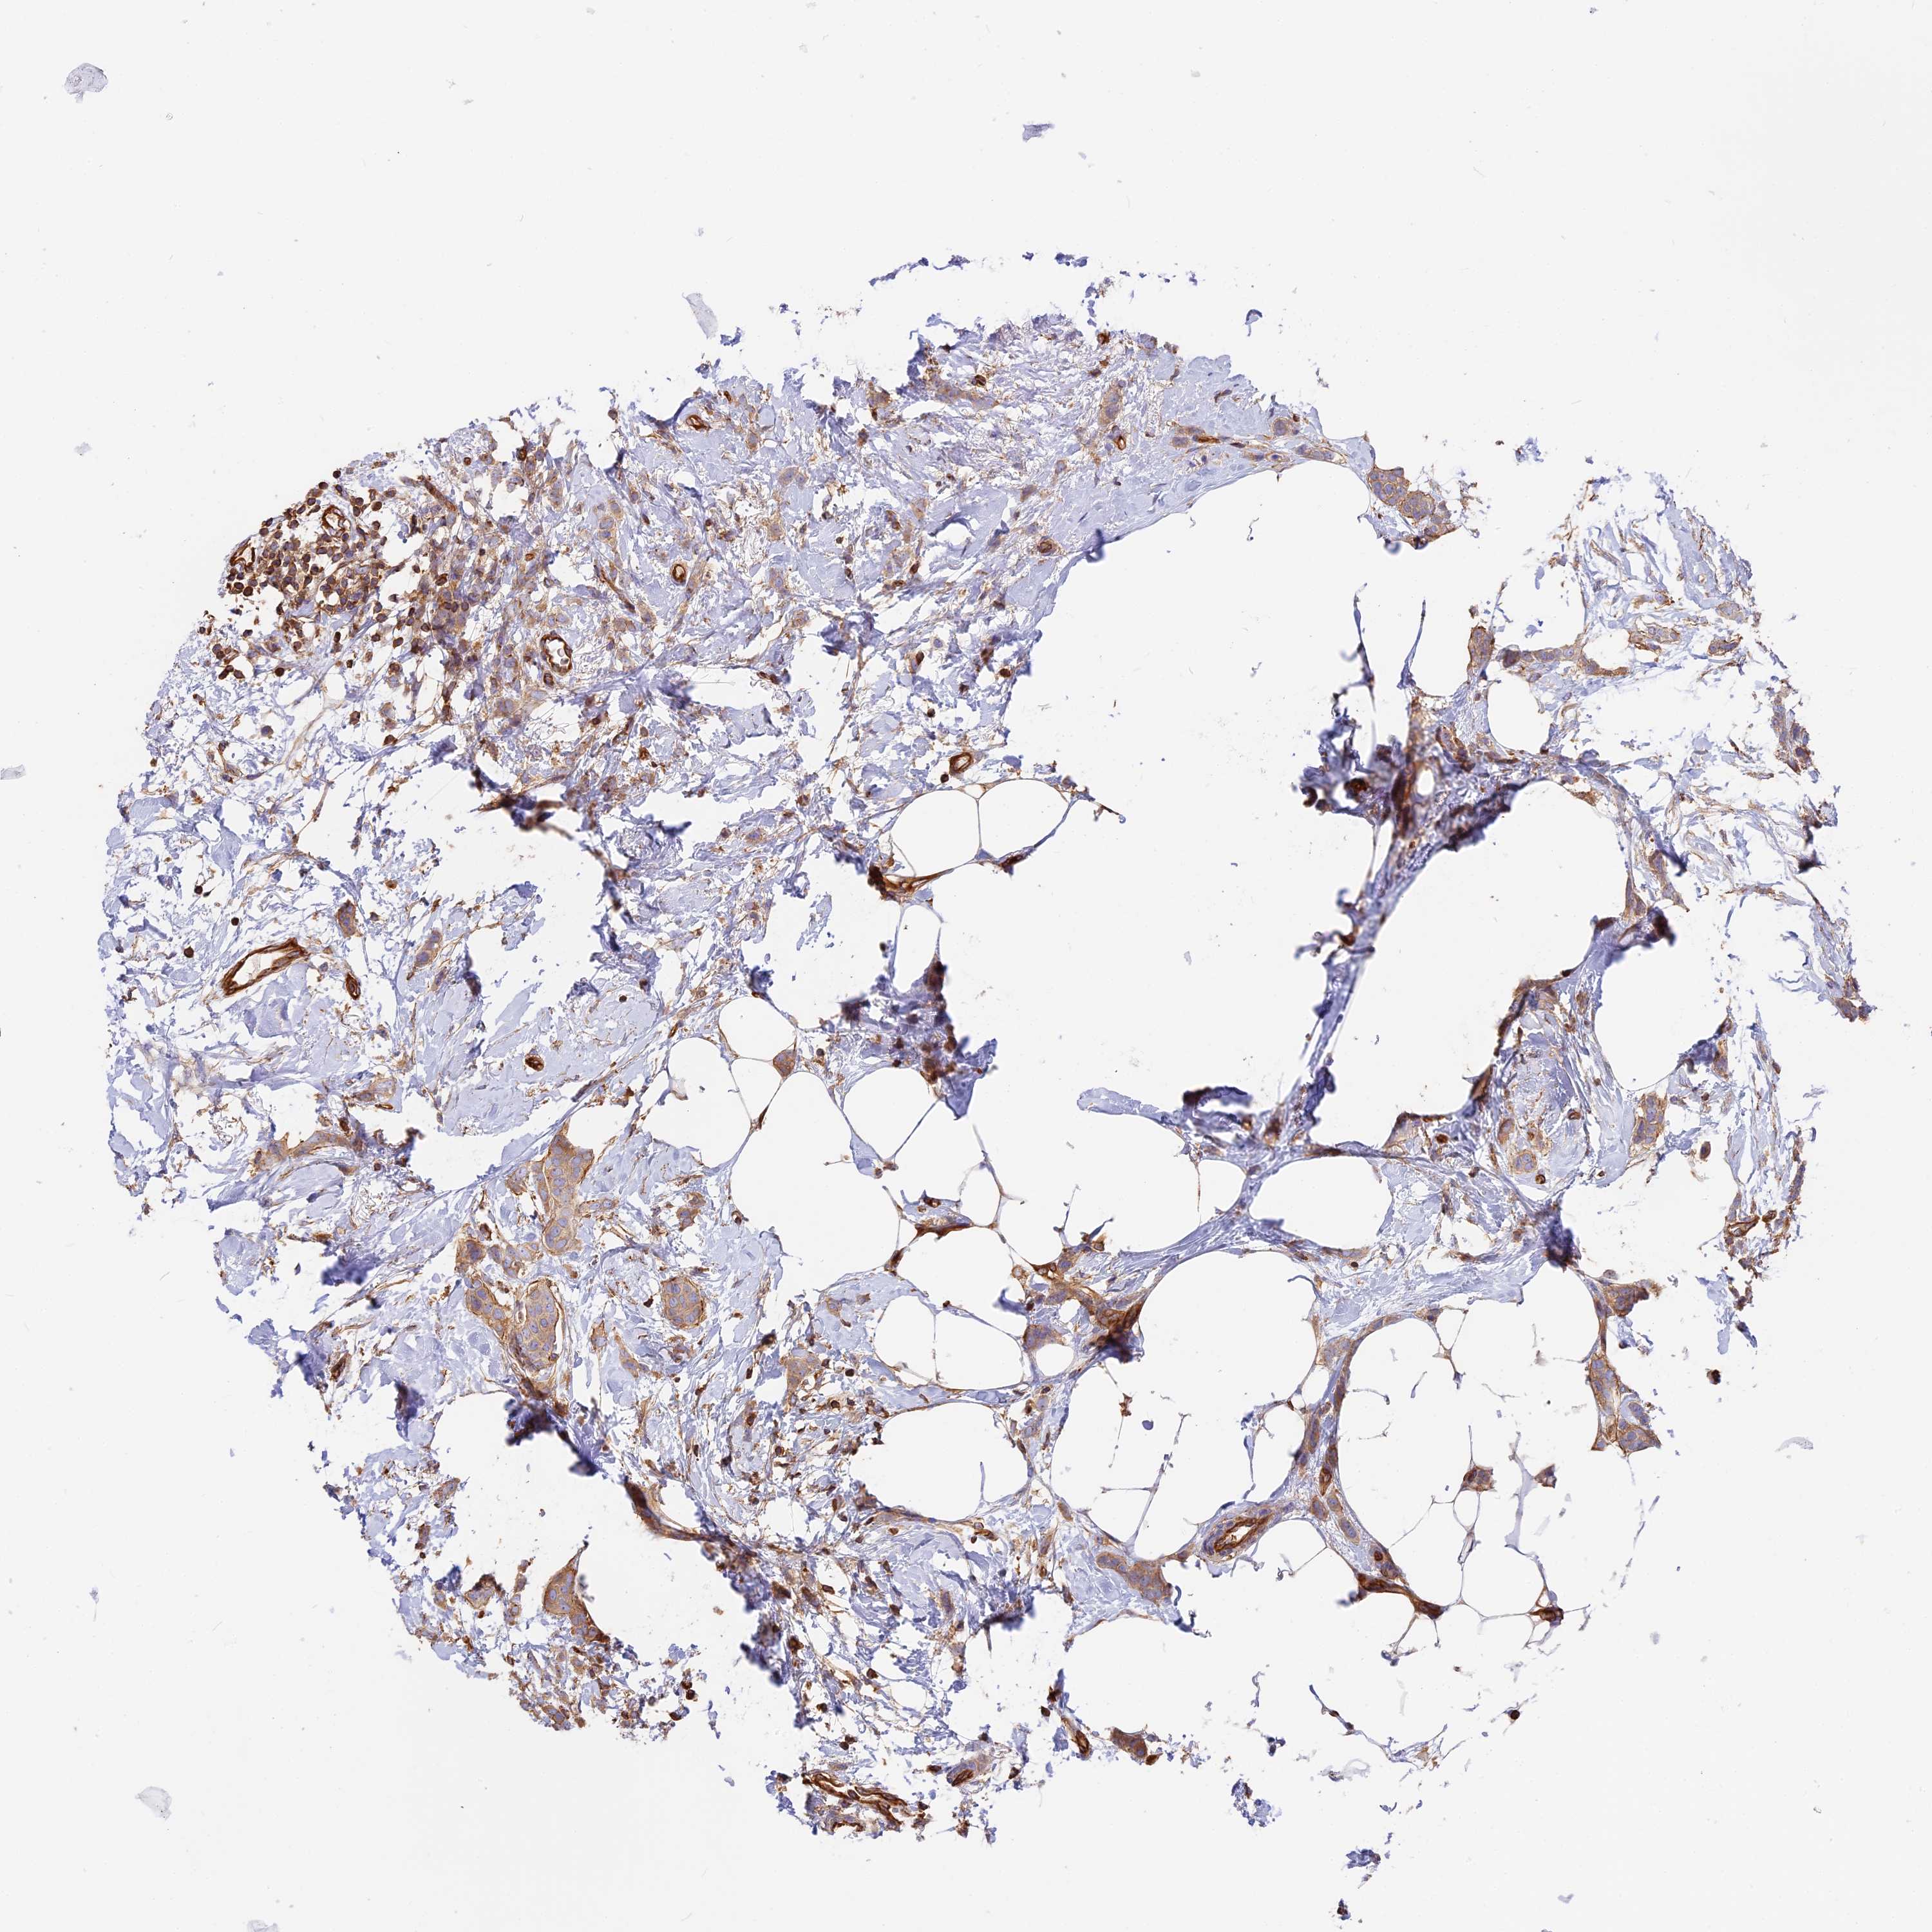

BRCA TCGA BRCA VALIDATION PROTEIN EXPRESSION